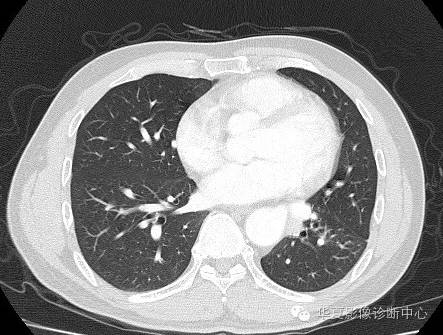

| 影像表现及分析: | 影像表现:定位左下叶;左下叶体积缩小,整体密度增高,支气管分布正常,其内见血管增多,但是走形正常,未见杂乱、迂曲的血管影;血管连向肺门下方软组织密度结节灶,结节与主动脉分界不清,增强后,见降主动脉发出异常粗大血管供血整个左下叶,左下肺动脉细小。 |

异常体动脉供应正常下肺基底段完整含义为起源于降主动脉的异常动脉供应下肺基底段,而基底段支气管树和肺实质正常,同时基底段肺动脉缺如或狭窄【大部分缺如(完全型),部分狭窄(不完全型)】;95%以上累及左下肺,因此也称为异常体动脉供应正常左下肺基底段。 病因尚未明确,可能是胚胎发育时期供应肺芽的背主动脉原始小分支退化不全,与肺实质形成异常连接,并影响肺动脉与肺血管床连接而导致此部位肺动脉发育不良,而支气管、肺组织的发育未受影响。本病的病理生理基础为左向左的分流,体动脉供应的肺组织充血,体循环的高压可增加肺血管床的压力和左心负荷,同时也增加肺循环量和压力而增加右心负荷,导致各种临床症群。本病可无临床症状,部分患者可有咯血、呼吸道感染、呼吸困难、充血性心力衰竭。 影像表现:左肺下叶体积缩小,整体密度稍增高,支气管树走形、分布正常,血管增多、稍增粗;增强后显示左下肺动脉幼小,甚至不发育;下叶由主动脉发出的粗大血管供血。 |